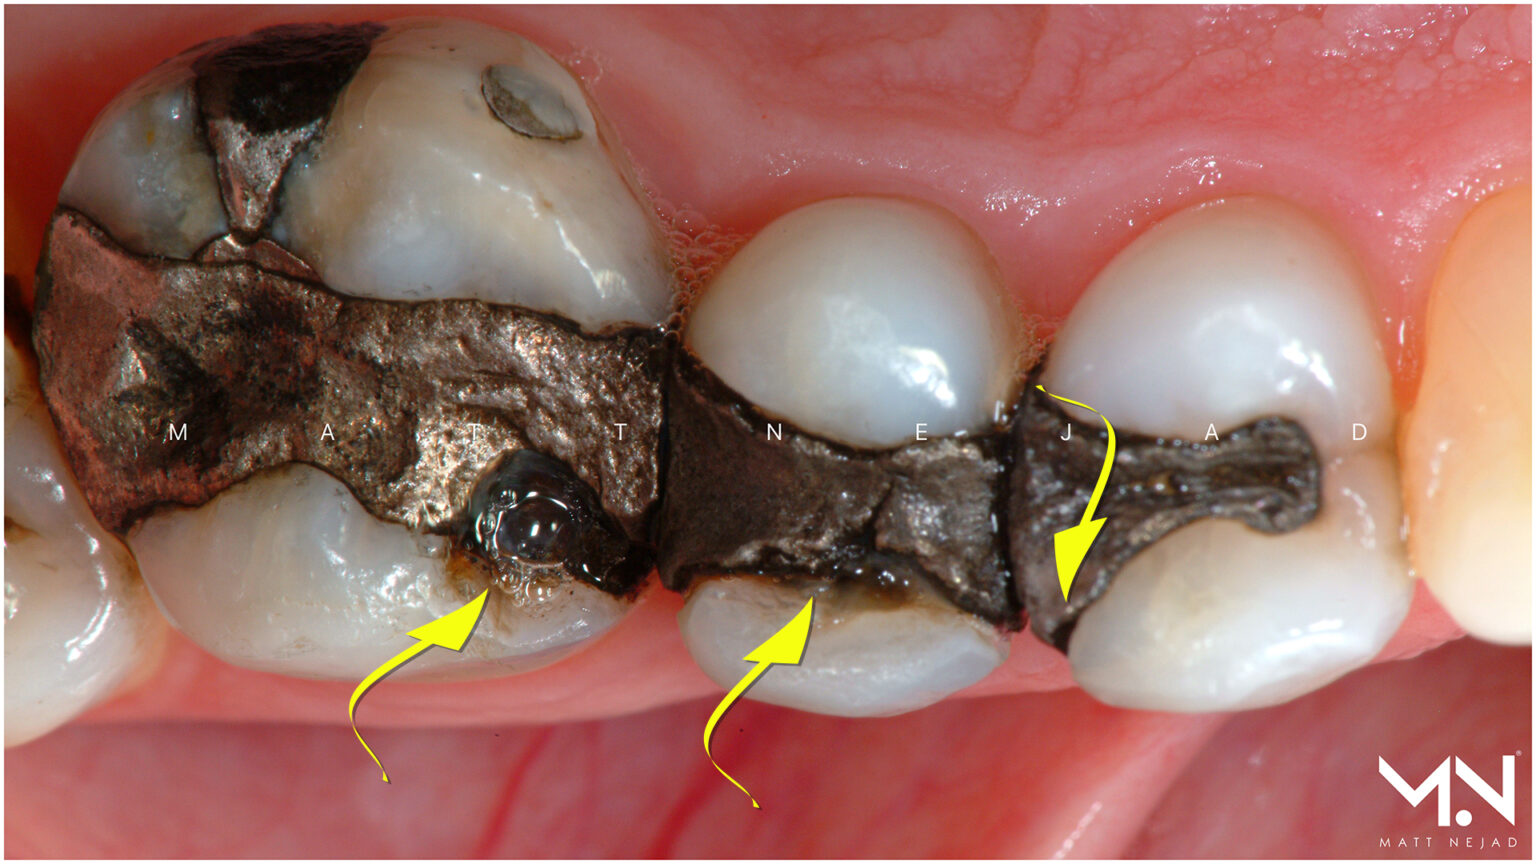

Tooth Fillings And Restorations - McGann Family Dental

mcgannfamilydental.comdental filling fillings tooth silver mercury removal process old restoration restorations mcgann after family underneath

mcgannfamilydental.comdental filling fillings tooth silver mercury removal process old restoration restorations mcgann after family underneath

Old Fillings, Decay & Broken Teeth | Smile Concepts

www.smileconcepts.com.aufillings old decay broken tooth

www.smileconcepts.com.aufillings old decay broken tooth

mckenzieriverdental.comReplace Silver Fillings With Natural Biomimetic Restorations

mckenzieriverdental.comReplace Silver Fillings With Natural Biomimetic Restorations

www.beverlyhillsladentist.comfillings teeth amalgam filling needing replacing